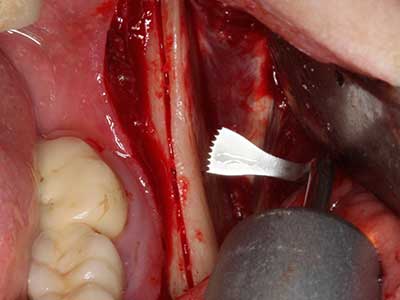

Индикация: Препарация близо до нерви

Когато се извършват хирургични процедури върху кост в непосредствена близост до чувствителни структури като кръвоносни съдове или нерви, ротиращите инструменти създават значителен риск за ятрогенно нараняване. Пиезоелектрическите апарати могат да бъдат от помощ при препарация на костно покритие и отстраняване на твърда кост близо до нерви, особено за оголване на нервите след ятрогенно нараняване, както и по време на латерализация на нервите за резекционни и реконструктивни процедури или поставяне на имплант (Фиг. 17-20). Лекият контакт между пиезонакрайника и нерва по принцип не води до нараняване, но ако действате непредпазливо с трионообразни движения или приставки за остатъчен костен субстрат, може да причините временно или перманентно увреждане на нерва. Въпреки това, рискът от увреждане се счита за много по-малък, отколкото при употреба на триони или ротиращи инструменти (Pereira, Gealh et al. 2014).